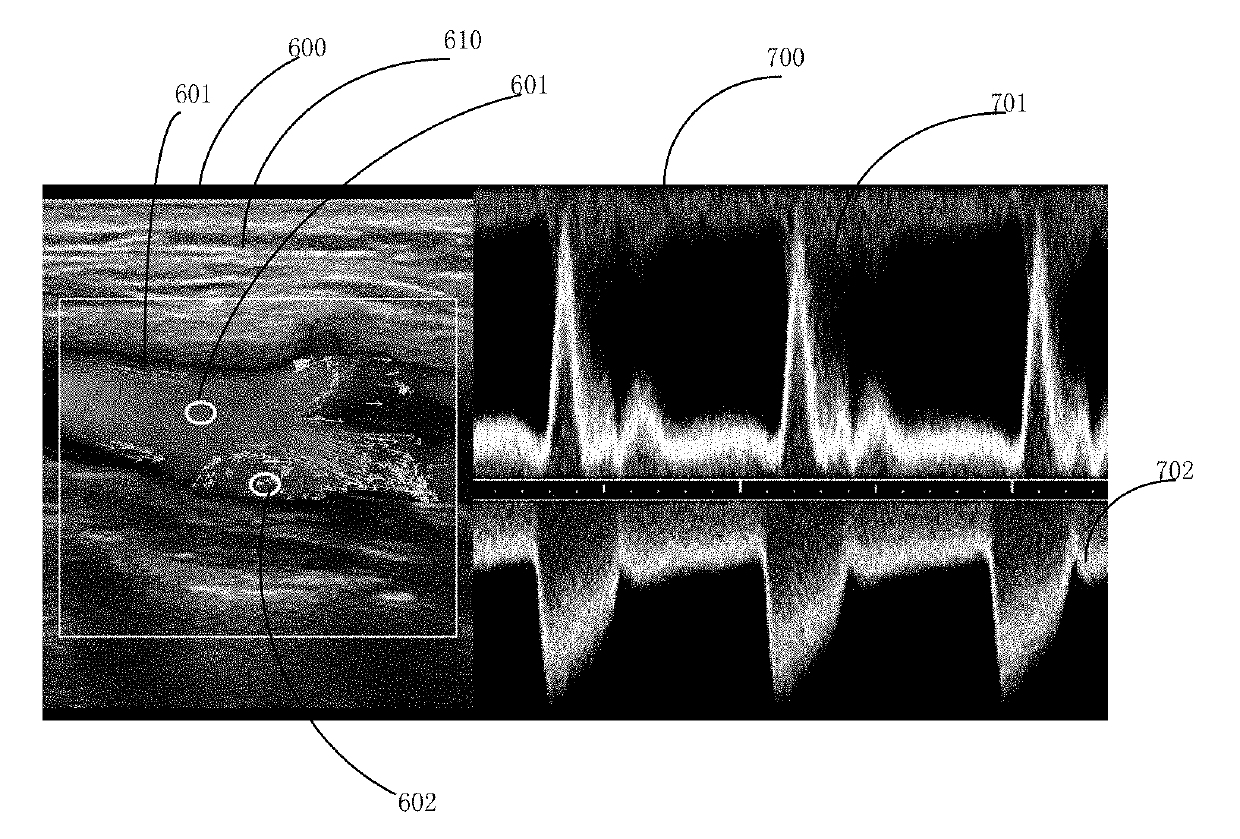

Method and System for Ultrasonic Fluid Spectral Doppler Imaging